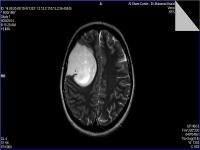

Medical imaging is an important investigative tool will help doctors to reach for the diagnosis of certain diseases, and the the advanced and high-quality imaging technologies are an important factor in maintaining the health of patients and accurate diagnosis of pathological lesions.